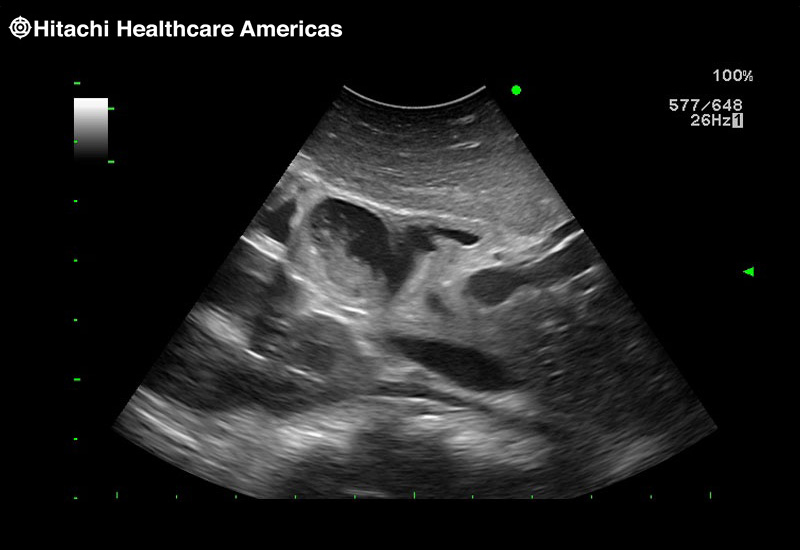

Superior guidance for all applications

Fujifilm Healthcare Americas is committed to designing tools that help surgeons navigate inside the human body and provide the necessary information to immediately make critical surgical decisions.

Fujifilm Healthcare's dedication to Surgeons provides outstanding ultrasound technology, professional support and the specialized tools necessary to best perform comprehensive real-time ultrasound imaging in Breast Surgery, General Surgery, Laparoscopic Surgery, Neurosurgery, Robotic Surgery and Surgical Oncology.

Recognized for our outstanding image quality, outstanding system reliability and intuitive use of cutting edge technology, Fujifilm Healthcare remains the standard in the field of Surgery.

Recognized for our outstanding image quality, outstanding system reliability and intuitive use of cutting edge technology, Fujifilm Healthcare remains the standard in the field of Surgery.

Imaging Clearly Defined

State-of-the-art digital architecture and advanced imaging features to redefine the capabilities of surgical ultrasound.